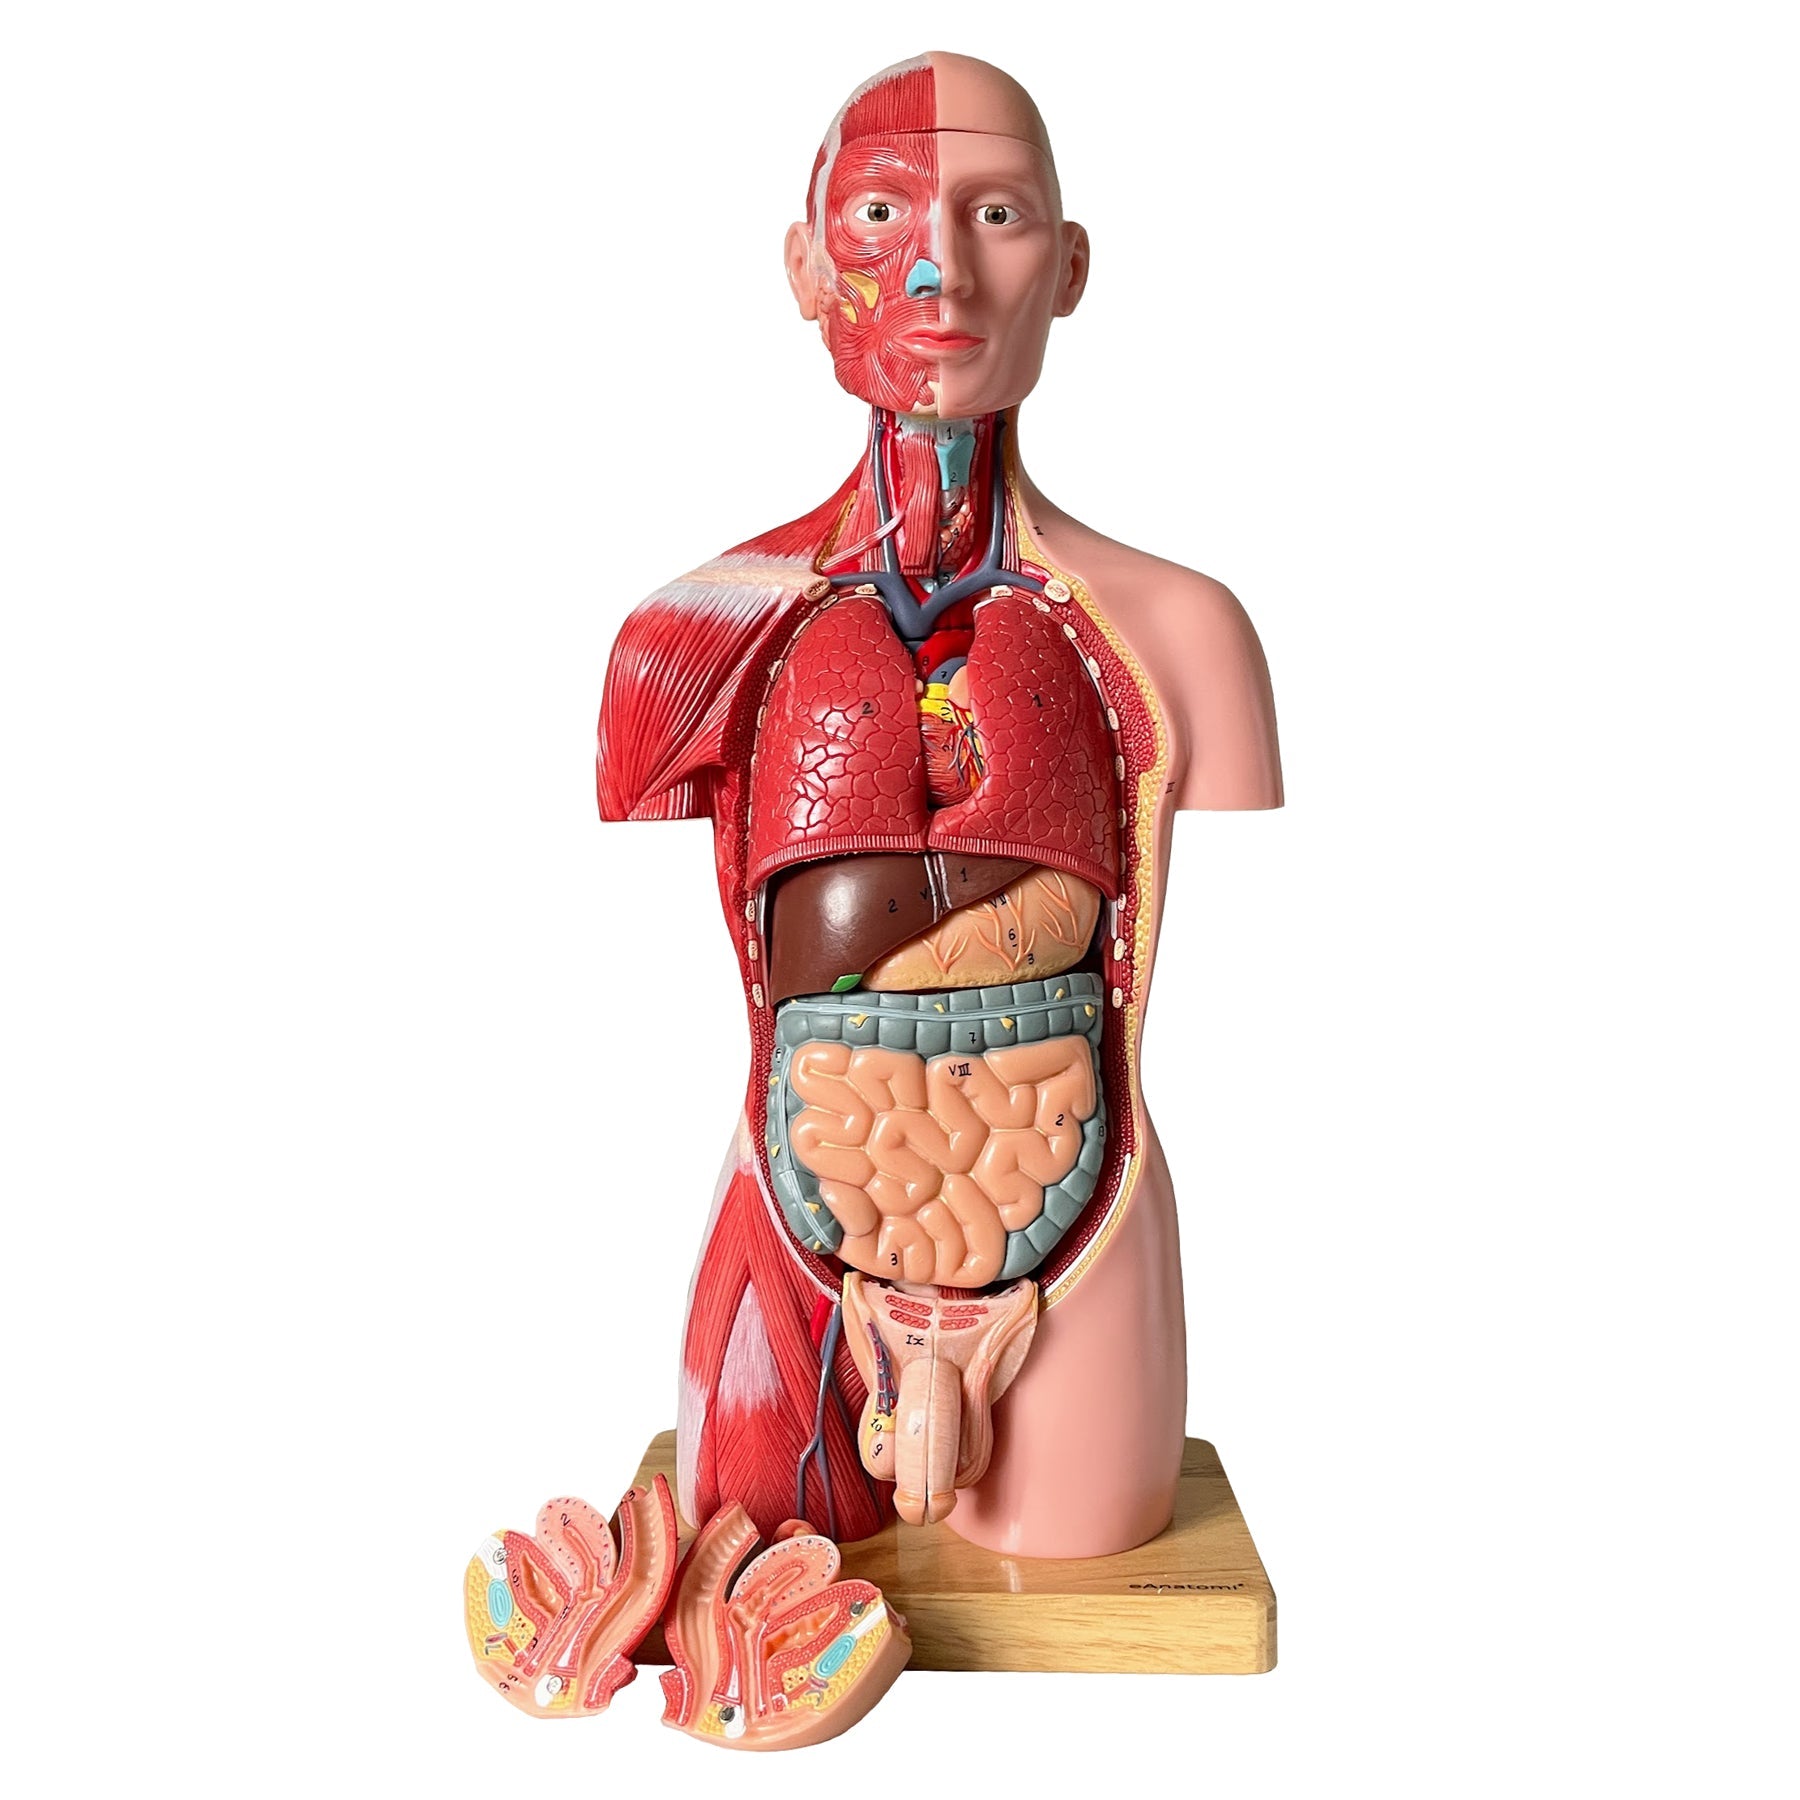

Anatomisk modell som illustrerar det sympatiska nervsystemet, sett i relief från höger sida av kroppen. Modellen är särskilt detaljerad kring plexus cardiacus och plexus sacralis.

Modellen väger 4,3 kg och följande mått

- Längd: 10 cm

- Bredd: 25,5 cm

- Höjd: 74 cm

Modellen levereras fast monterad på grönt underlag